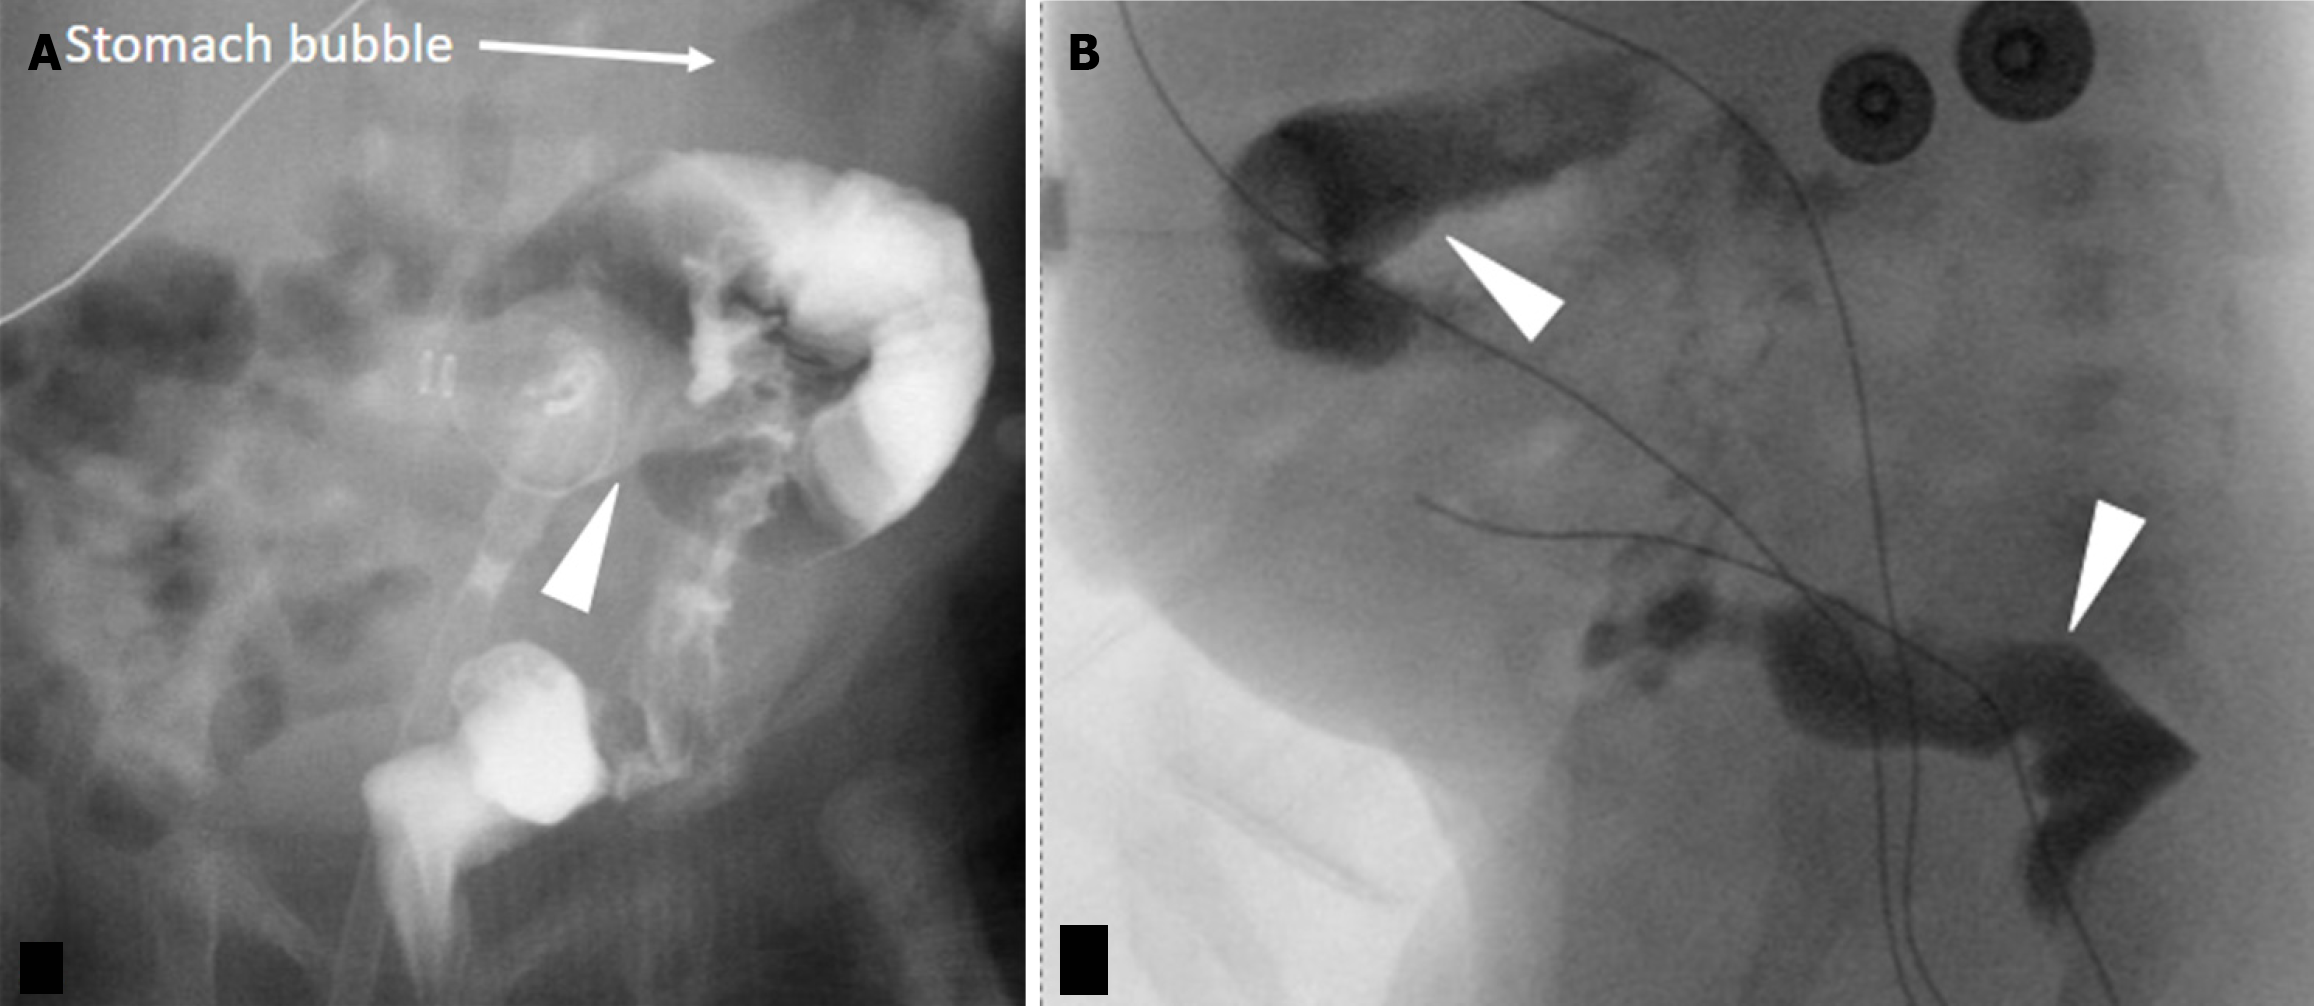

Figure 6 Malposition of G-port of gastrojejunostomy tube into the duodenum.

A 20 year old male with increased abdominal distension and bilious output from G-port of gastrojejunostomy tube. A: Frontal radiograph shows that the G-port (black arrow) has migrated into the right upper quadrant from its ideal location in the left upper quadrant suggesting peripyloric position. The G-port should be in the left upper quadrant; B: Oblique post injection radiograph demonstrated intraluminal opacification of the duodenum (arrow) without opacification of the stomach (arrowhead) confirming a migrated G-port balloon into the pylorus or proximal duodenum.